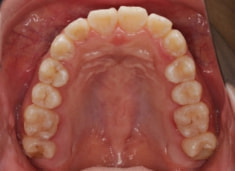

治療後(1年12ヶ月後)